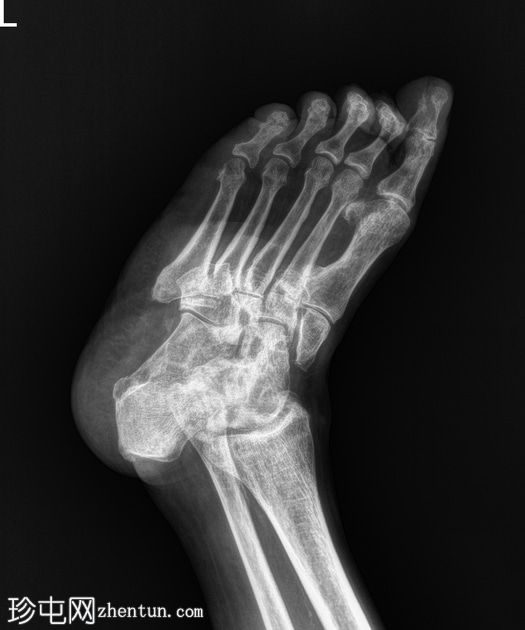

正位片

双足均符合典型的夏科氏关节病特征,该患者为已知糖尿病患者。

该病表现为骨质疏松、骨硬化(密度改变)、跗骨碎裂和破坏、关节内游离体(碎屑)、软组织肿胀和关节积液(扩张)、中足结构紊乱以及跗跖关节错位(脱位)。

X线平片未见气性坏疽或化脓性关节炎的证据。